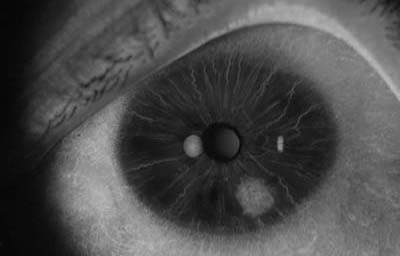

Melanoma difuso del iris

Archivo Fotográfico Dr. Francisco Barraquer.

En la forma difusa, se aprecia una capa plana, irregular, de células pigmentadas o no, con un compromiso del iris confluente o multifocal; representa el 10% de todos los melanomas del iris. Su diagnóstico es difícil y demorado, porque frecuentemente los pacientes están siendo tratados por el cuadro de glaucoma secundario que generan. Clínicamente lo mas frecuente en su presentación es encontrar heterocromía hipercrómica unilateral y glaucoma secundario. Como dato importante, los melanomas difusos comparandolos a otros melanomas del iris, muy frecuentemente están compuestos por células epiteliodes, que tienen poca cohesión y se dispersan con facilidad en el humor acuoso, haciendo siembras en el trabéculo y estroma iridiano, y por esta razón son considerados de alto riesgo para metástasis. (33)